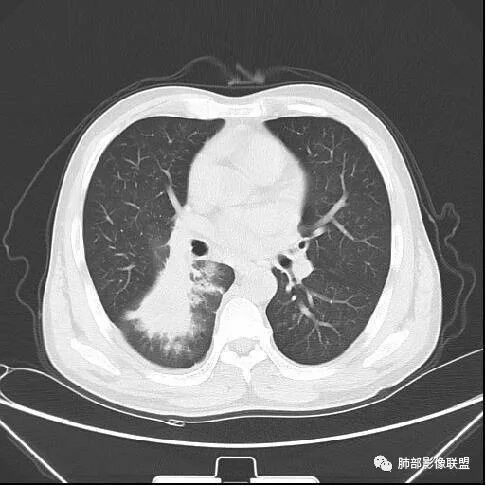

南边:紧贴着斜裂过来的一个病灶,它的特点是:外围大,内带小。它整个下叶背段体积与对侧相比稍微缩小一点,但是缩小地不是很厉害。外支朝前下走了,仔细看血管,肺动脉走行自然,直达远端。远端实变区是肉芽肿成分,稍微有一点低密度,没有明显坏死,稍微有一点点坏死。而且附近有很多卫星灶,附近很多斑片影,有一些明显有气道壁增厚,细支气管炎的特点,还有就是下叶其他段很多斑片状影。换个角度,第一如果是肺癌,刚才看到PET-CT提示肺癌伴阻塞性肺炎,这个是不符合的。第二如果是肺癌阻塞性肺炎,近端血管肺动脉走行不会那么自然集聚的,这个是不符合的。理由是:如果这个病灶是肺癌,那么明显属于中央型肺癌,中央型肺癌的特点是近端大,远端小,近端是一个肿块,远端阻塞,远端阻塞是阻塞性炎症或者不张,它应该体积缩小,斑片状实变,不会这么密实。刚才有老师提到支气管,这个片有缺陷的地方,给的图像好像那层,如果把其他图像拿开再重叠一下。

如果是单纯看这幅图像,会觉得背段外侧支气管分支堵塞的,但是看下面这层图

南边:你就发现外侧支气管朝下走的分支非常自然,通畅的。